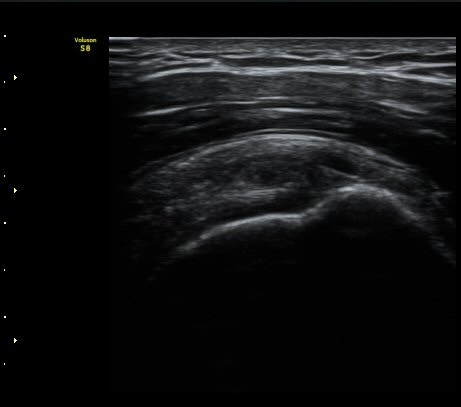

ÀÌµÎ¹Ú±Ù°Ç È¾´Ü¸é°Ë»ç¿¡¼­ ƯÀÌ ¼Ò°ß ¾øÀ½

(no specific abnormal findngs with transverse scan of biceps tendon) »çÁø 1, 2